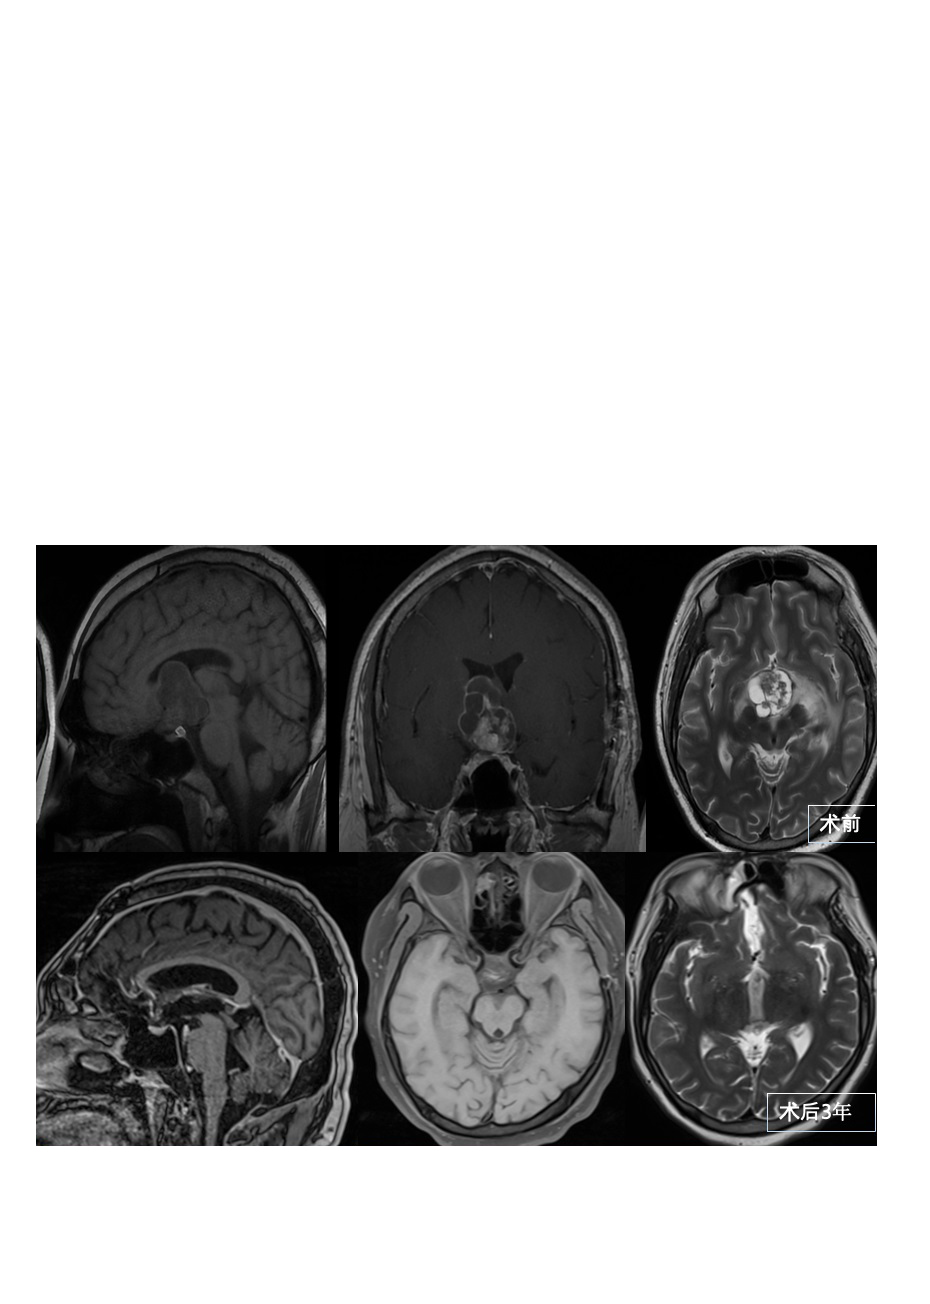

30多岁男性颅咽管瘤全切术后3年没有复发

妻儿陪伴幸福满满

病史摘要:2018年,高先生无明显原因出现精神疲劳,易入睡。在过去的一年里,他的体重增加了约20公斤。2019年6月开始多尿,每天量5000ML,伴多饮。2019年9月,发现鞍区占位,考虑颅咽管瘤。2019年9月,在当地医院行脑病变切除。术中将同侧视神经肿瘤后移,一间隙见肿瘤组织。肿瘤组织为视神经增厚。一些肿瘤沿着视交叉肿瘤较明显的部分被取下,活检。快速病理结果显示:视神经胶质瘤,更有可能考虑低级别胶质瘤。术后给予对症支持治疗,病情好转出院。患者意识清晰,双眼视力模糊,无其他不适症状。

由于肿瘤仅部分切除,高先生知道,这个肿瘤不会就此停止生长。他面临着肿瘤随时恶化增大的风险。迷茫之下,高先生夫妻两通过搜寻各种治疗信息,联系到INC国际,寻求国际专家的帮助。

手术记录:2019年11月INC德国巴特朗菲教授主刀,进行了高难度的全切手术,额基底中线开颅经终板入路全切肿瘤手术。

术后情况:手术成功,高先生的身体逐渐恢复了健康。“原先一天两次垂体后叶素3单位皮下注射,现在停了改为弥凝,其他都正常。也可以正常上班。”三年过去了,他没有再次复发。他的生活也重新回到了正常的轨道上,他能够像以前一样工作、照顾家庭,与家人一起享受生活的美好。即使一直在接受着药物治疗,高先生仍幸福无比。